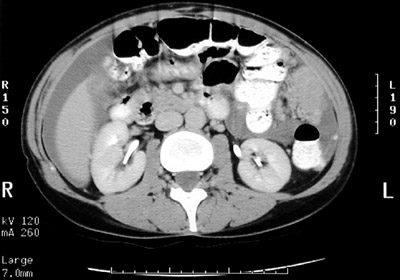

| This abdominal CT scan demonstrates a mass lesion on the abdominal wall from seeding of metastases from an ovarian serous cystadenocarcinoma. Often, the first sign is abdominal enlargement with ascites. Note the ascitic fluid seen here around the liver and elsewhere. |